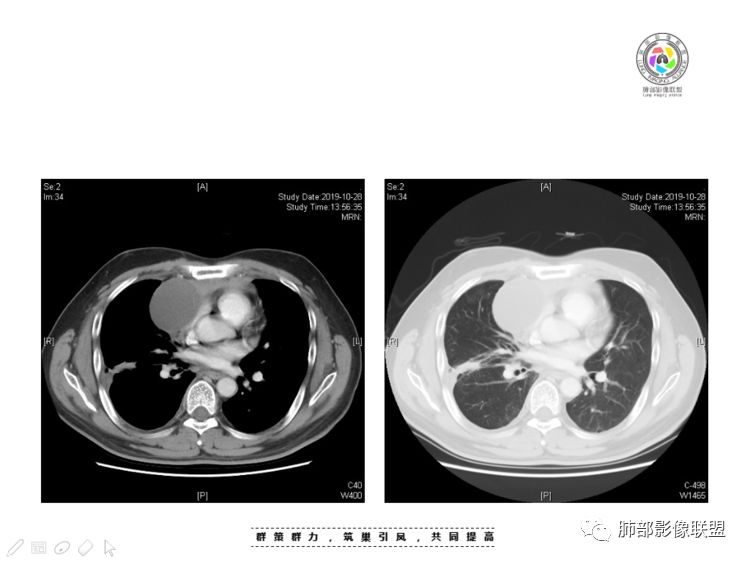

穿越七海的风:右前纵隔占位,恶性肿瘤,生殖来源?右肺实变是占位or肺不张?考虑为部分肺不张FeNo:右前纵隔占位,右肺结节,胸膜凹陷,小尾巴,右肺不张,考虑恶性杨旭华:恶性,前纵隔肿物,与血管关系密切,上腔静脉变窄,右肺野一元论考虑叶间裂增厚,恶性胸膜间皮瘤可能大小丽:到底是纵隔来源还是胸膜来源?我怎么倾向于胸膜来源,和叶间胸膜关系密切,而且纵隔内上腔静脉是向内侧推移。胸膜肿瘤(间皮瘤?SFT?)包裹性胸腔积液?马春平(张家港市一院胸外科):前纵隔占位,左无名受压,右大量胸腔积液可能是胸导管汇入处侵犯受压,考虑纵隔鳞癌孙冰伟:右上纵隔占位,也感觉和叶间胸膜关系密切,右侧胸膜局限性增厚,考虑恶性可能性大灵:前纵隔占位,血性胸水,胸膜凹凸不平,查见肿瘤细胞,结合免疫组化考虑胸腺癌。鉴别胸膜间皮瘤。采莲:右前上纵膈旁可见类圆形肿块,纵隔血管内移,感觉来源于胸膜,肿块内密度低,似水样密度,右侧胸膜广泛增厚,少量胸腔积液。心包少量积液。考虑胸膜间皮瘤,鉴别肺癌并胸膜转移?水晶石头:患者中年男性,胸闷15天。有“高血压、慢性肾小球肾炎”病史。查肿瘤标志物正常,胸水提示渗出液,胸水病理查见瘤细胞。胸部CT:右肺上叶后段结节、斑片影,见胸膜牵拉、包裹积液及部分纤维条索灶,似见卫星灶,右侧胸膜增厚。前纵隔脂肪密度增厚,右侧可见类圆形低密度(液体)肿块,边缘光滑。综合考虑右肺腺癌并胸膜转移,结核可能。周太狼:考虑纵隔胸膜来源肿瘤,恶性,胸膜间皮瘤伴转移?徐飞:中年男性,影像为右侧胸腔及叶间积液,叶间胸膜增厚轻度强化。前纵隔右侧心缘旁团块,可见坏死。胸水见癌细胞,综合考虑恶性,胸腺癌伴转移。小赵:中年男性,血性胸水,常规查见癌细胞,李凡他实验阳性。胸部CT示前纵隔见不均匀密度影,与邻近大血管分界不清,囊变坏死明显,增强扫描呈不均匀强化,心包及右侧胸膜增厚,并心包及右侧胸腔少量积液。综合考虑胸腺癌。右肺中叶病变周围见多发纤维条索,支气管部分进入病灶,考虑炎性病变。流心明智:患者,男性,50岁。胸闷15天。高血压20年,慢性肾小球肾炎15年。肿标正常,胸水提示渗出液,胸水查见癌细胞。胸部CT:右肺肿块影,斑片影,索条影,可见胸膜牵拉、多发包裹积液,纵隔上腔静脉受累,心包受累。综合考虑:ROSE似腺?考虑右肺腺癌并胸膜转移,心包受累。鉴别胸腺Ca、淋巴瘤,纵隔病变不懂,等老师们精彩分析。王秀仙:前纵膈囊实性肿块,与纵膈分界不清,心脏大血管及上腔静脉受压向内后移,右侧后胸膜、侧胸膜增厚,右侧叶间裂不规则增厚,心包积液,根据腔静脉移位情况,考虑纵膈胸膜来源恶性肿瘤,胸膜间皮瘤?鉴别胸腺癌并胸膜转移。高广飞:上纵隔占位,右侧叶间胸腔积液,需考虑恶性自信人生:多发囊实性病灶,包裹性积液,考虑胸膜来源 只是没有看到壁结节,恶性胸膜间皮瘤巴伟:前上纵隔占位,胸膜及心包结节,考虑胸腺瘤或癌,右肺病灶,先考虑陈旧炎性病变。Lenle董:前纵隔占位,部分边缘模糊,病灶内囊变?坏死?上腔静脉受侵,考虑胸腺癌;叶间片状影,强化明显,炎性考虑。常志强:前纵隔囊实混杂密度肿块,边界不清,实性部分强化明显,结合胸水内见癌细胞,考虑恶性肿瘤伴转移。飞鹰行动:前纵隔占位,软组织密度及囊性密度,实性部分密度均匀,致密,病灶与周围血管分界不清,增强后病灶强化有类似不温不火强化,部分血管受侵犯,右肺见肿块样病变及条索状病变,一元论,考虑淋巴瘤,二元论,考虑胸腺瘤B2—B3伴右肺病变。尽量一元论考虑,淋巴瘤可能。看图说话:右肺索条病灶,边缘膨隆,胸膜牵拉,考虑右肺癌伴胸膜转移。晨:前纵隔囊实性肿块,与纵隔分界不清,右侧后胸膜、侧胸膜增厚,右侧叶间裂不规则增厚,考虑纵隔胸膜来源恶性肿瘤,考虑胸腺癌并胸膜转移。丽:中年男性,前纵隔囊实性肿块,呈偏心性生长,临近大血管受压推移,增强后实性部分不均匀强化,心包可见条形积液,考虑胸膜来源恶性肿瘤,胸腺癌可能大。另右肺多发斑片状高密度影及实变密度影,实变影呈均匀强化,右侧胸膜局限性增厚,考虑炎性病变。小飞:右前纵隔囊实性占位,实性部分明显强化,右侧叶间胸膜增厚,右侧胸腔积液,心包积液,考虑恶性胸腺瘤!尘缘:支持恶性胸腺瘤(囊实性肿块,实性强化,且侵犯纵隔,脂肪间隙模糊)伴肺内及胸膜转移。浪迹天涯:考虑侵袭性胸腺瘤——胸腺前纵隔占位,周围脂肪间隙模糊不清。尘缘:不除外另一种可能:二元,肺内腺癌合并胸膜转移,纵隔的畸胎瘤可能。一米阳光:晨读中年男性,右肺结节影,叶间裂及胸膜增厚牵拉,右侧胸水。心包多发结节改变。胸水查见癌细胞。考虑,腺癌并转移。鉴别,胸膜间皮瘤并转移前纵隔囊实性占位,二元考虑。心灵鸡汤:老年男性,右肺中叶外段长条状软组织密度影,边缘膨隆,邻近胸膜牵拉,部分胸膜有栽脏,右中叶外侧段支气管堵塞,常规考虑恶性肿瘤,腺癌可能,结核、鳞癌不除外,另右肺上叶斑片影,小叶性肺不张?右前纵隔囊实性不规则形密度影,其内见部分脂肪样极低密度影,与邻近血管边界不清,心包外膜有侵犯,增强未见纵隔窗平扫,实性及分隔见增化,其内低密度影未强化,考虑低度恶性纵隔肿瘤,间皮瘤可能,畸胎瘤、淋巴瘤待排,建议支气管镜及穿刺活检。曹志勇:右前纵隔考虑来源于胸膜的恶性肿瘤,右肺内病灶考虑鳞癌,二元德芙~云味:中年男性,右肺见结节、斑片影,右侧包裹积液、胸膜牵拉,纤维条索,前纵隔囊性占位,考虑腺癌、并转移。欧阳英:右前中纵隔囊实性肿块及右肺内结节灶,支持恶性肿瘤,胸腺癌并肺内转移可能张延军:前纵隔见不规则软组织影,密度不均,右侧缘见囊变区,纵膈及侧胸壁胸膜增厚,增强呈不均匀强化,右肺中叶见结节灶,近段支气管阻塞,叶间胸膜不规则增厚,考虑1:右肺中叶腺癌伴纵膈及胸膜转移;2:前纵膈侵袭性胸腺瘤并胸膜侵犯,中叶炎性改变?彭君:老年,前纵隔占位 ,坏死边缘清, 侵犯心包 右侧胸膜及叶间胸膜结节 ,少量胸水, cea不高 ,考虑恶性, 间皮瘤可能 ,转移待除外。毛勤香:恶性没问题,胸水查见癌细胞,一元还是2元,右肺中叶肿块,边缘毛糙,局部似有毛刺,周围有粘连,右侧胸膜腔少量积液,胸膜增厚多发结节,含叶间裂结节,纵膈脂肪间隙模糊,纵膈胸膜增厚,心包增厚积液,右前那个类圆形低密度肿块,纵膈血管内移,我考虑胸膜来源可能性大,综合考虑,一元肺腺癌并多发转移,二元考虑胸膜间皮瘤并多发转移,肺内炎症不张。

2、前纵隔内病灶囊实性混杂密度病灶,囊性病灶主要位于右侧,张力较高,有分隔影,囊壁右侧缘光整,病灶左侧实性部分边界不清明显强化,病灶肺瘤交界面大部分边界清楚,部分模糊。

前纵隔肿块伴囊变坏死常见以有胸腺瘤、胸腺癌、淋巴瘤和生殖细胞肿瘤。

胸腺瘤/胸腺癌:病灶内那么大的囊,常规考虑B型以上胸腺瘤,囊内有分隔影,病灶周围脂肪间隙模糊,常规考虑侵袭性胸腺瘤或胸腺癌,若侵袭性胸腺瘤,常侵犯胸膜、心包,很少累及肺。胸腺癌易侵犯胸膜、肺并纵隔淋巴结及远处转移。但肺内腺癌形态更符合原发灶。胸膜及叶间裂转移则即可来自肺,也可来自胸腺癌。